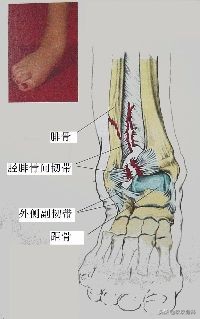

(二)外侧结构

外侧副韧带

- 距腓前韧带

- 距腓后韧带

- 跟腓韧带

- 跟距外侧韧带

2.踝外侧副韧带损伤

A.单纯韧带损伤

- 踝外侧副韧带的牵扯及部分断裂特点:没有明显关节不稳

- 踝外侧副韧带完全断裂特点:有明显关节不稳

- 常有一时性脱位或半脱位多合并关节囊的撕裂